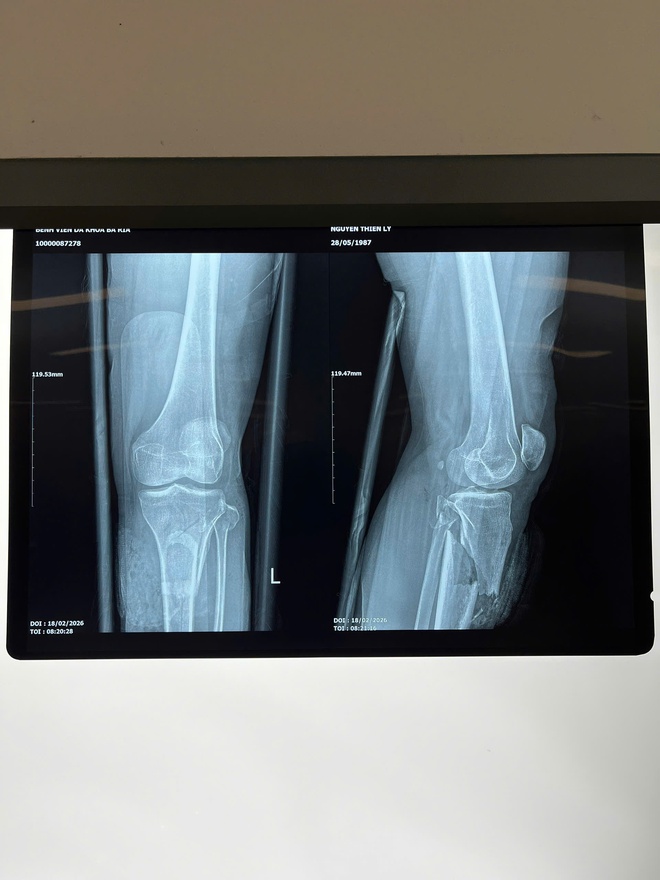

Ảnh chụp cho kết quả xương cẳng chân gãy phức tạp và vết thương sau phẫu thuật thành công

Kết quả, chị L. bị gãy hở độ 3C 1/3 trên xương chày trái, gãy đầu trên xương mác trái, đứt dập động mạch khoeo, tĩnh mạch khoeo, dập thần kinh chày, đứt dập cơ khoang sau sâu cẳng chân trái…